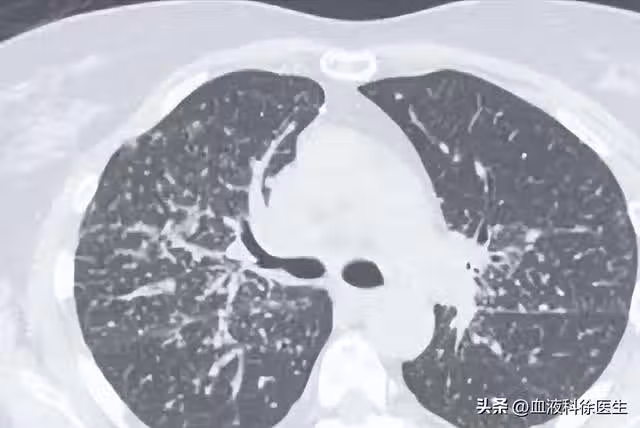

55歲男子5月體檢發現肺結節,年底就肺癌晚期,醫生:警惕肺結節

這便可以解釋為什麼王叔叔身邊的許多同事也被發現有肺結節,因為肺結節的發病率在人群中確實不低,預計隨著吸菸、空氣污染及人口老齡化的影響,檢出率會進一步升高。

既然肺結節的檢出率這麼高,那麼究竟是什麼原因導致了早期肺癌或是肺結節的發生呢?

一、早期肺癌——肺結節的病因